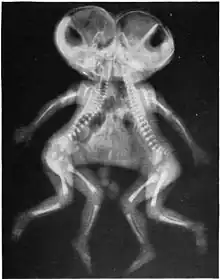

X-ray of conjoined twins, Cephalothoracopagus.

• Cephalothoracopagus: Bodies fused at the head and thorax, with two faces facing in opposite directions, or sometimes with a single face and an enlarged skull.[13][15]